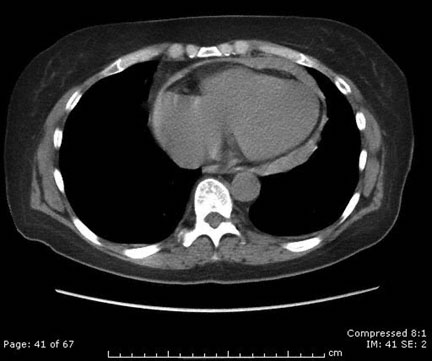

A 27-year-old man comes to the office because of a 2-day history of moderate chest pain and shortness of breath. He also has a 1-week history of a cough and low-grade fever that have not improved. He has no personal or family history of major medical illness. Temperature is 38.0°C (100.4°F), pulse is 92/min, respirations are 20/min, and blood pressure is 95/65 mm Hg. Pulse oximetry on room air shows an oxygen saturation of 97%. The lungs are clear to auscultation. Distant heart sounds are heard, and an anterior friction rub is heard and palpated. Results of laboratory studies, including complete blood count, and serum concentrations of electrolytes, urea nitrogen, and creatinine, are within the reference ranges. CT scan of the chest is shown. Which of the following is the most likely cause of these findings?